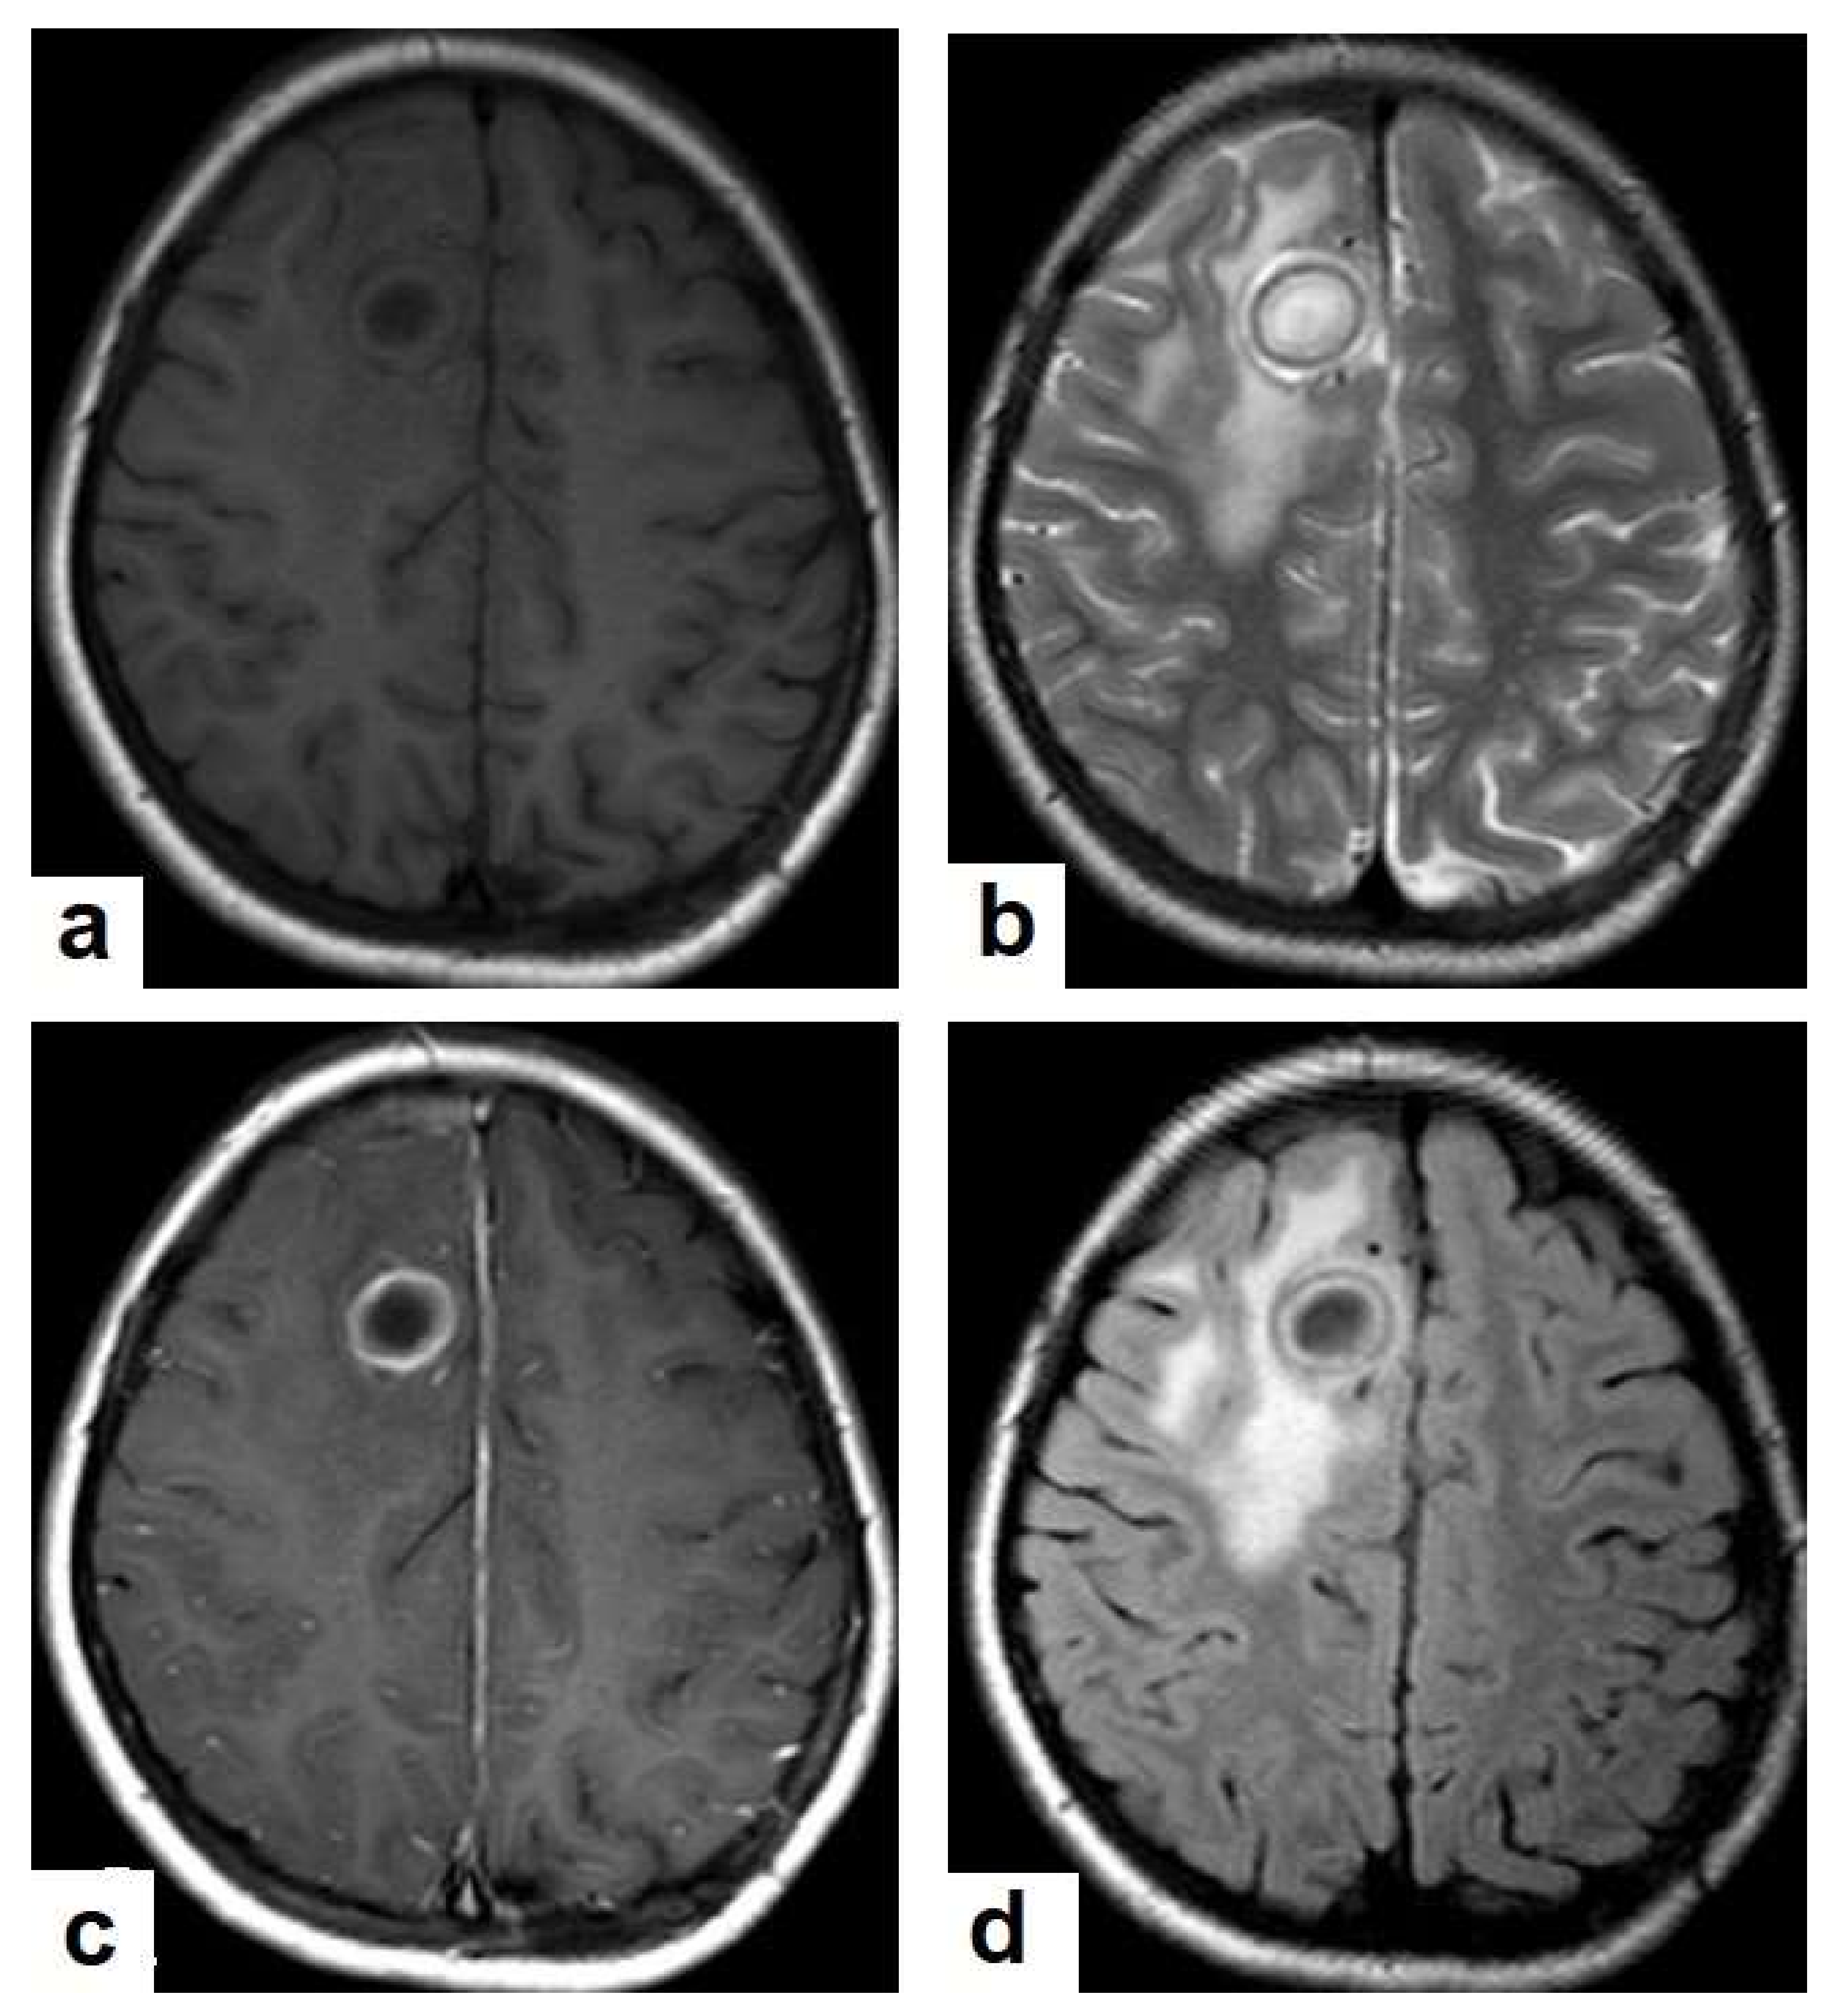

• Tuberculous abscesses (Figure 15, Figure 16 and Figure 17) are an infrequent pattern of brain TB, which are present in immunocompromised and elderly patients. They occur either due to the progression of cerebritis or the liquefaction of tuberculoma. On a brain CT, it occurs as a low density area with ring enhancement after contrast administration and the surrounding low density area of edema. On a brain MRI, it appears as a circular or elliptical area of low intensity with ring enhancement after contrast administration and surrounding low intensity area of edema on T1WIs and high intensity area with a high intensity surrounding edema. Tuberculous abscess is a difficult differential diagnosis of a pyogenic abscess, pilocystic astrocytoma, and other cystic lesions. MR spectroscopy may help in differentiating tuberculous from a pyogenic abscess [27,33].

Figure 16. Tuberculous abscess in the right cerebrum of a 13-year-old female. Selected images of brain MRI (a) T1-weighted image (WI), (b) T2-WIs, (c) T1-WI with contrast, and (d) FLAIR-WI. The images show a well-defined lesion in the right cerebral hemisphere with low-signal-intensity content and a high-signal-intensity capsule on T1WI, which appear as high-signal-intensity content and a low-signal-intensity capsule on T2WI (b); there is marginal enhancement on T1WI with contrast administration (c), and there are low-signal-intensity contents and a high-signal-intensity capsule on FLAIR (d). Obvious grade-2 vasogenic oedema around the lesion on T2WI and FLAIR.